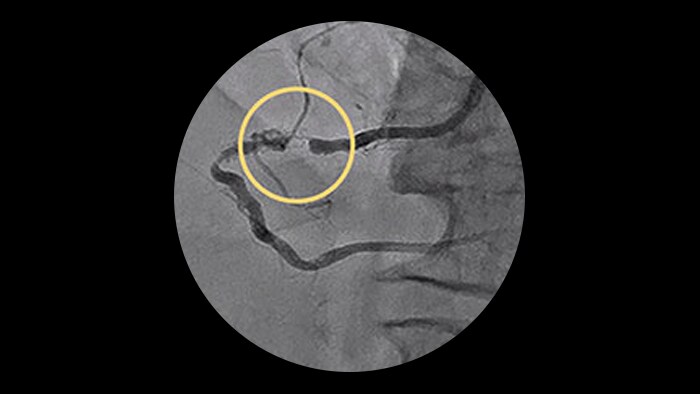

ELCA Success and safety rates

| Study | Lesion type | Technical success | Procedural success | MACE Rates* |

| Bilodeau | Calcified and complex coronary lesions | 92.0% | 93.0% | 8.0% |

| | Calcified, uncrossable, resistant coronary lesions | 95.5% | 95.5% | 8.0% |

| Pratsos | Crossable coronary lesions | 98.1% | 99.0% | 0.0% |

*Total occlusions traversable by a guide wire.